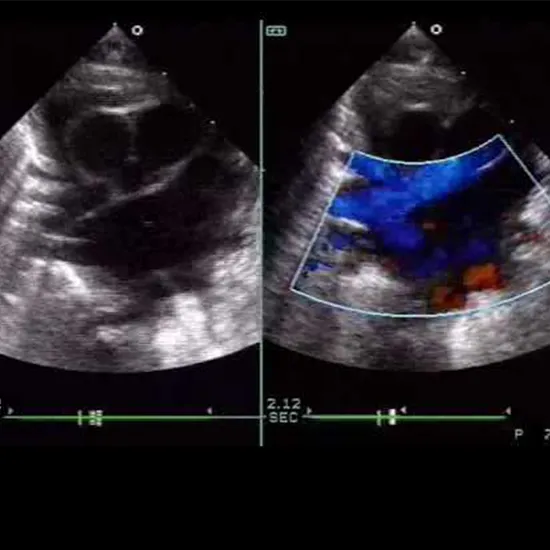

A pediatric cardiologist will use echocardiography (also known as an echocardiogram, echo, or heart ultrasound) to get moving pictures of your child's heart. It can provide information to the doctor about the heart's ability to contract as well as any heart anomalies, such as holes or narrowed valves.

The echocardiography can identify valve form, motion, narrowing, or backward flow, as well as structural abnormalities of the heart (holes between the chambers, fluid around the heart, the mass inside the heart, etc.)

• A picture is made by the transducer using sound waves that are reflected off the various surfaces of a child's heart.

• The sounds you might hear from the echo machine are the sounds of the blood moving through the heart's chambers and the valves opening and shutting.